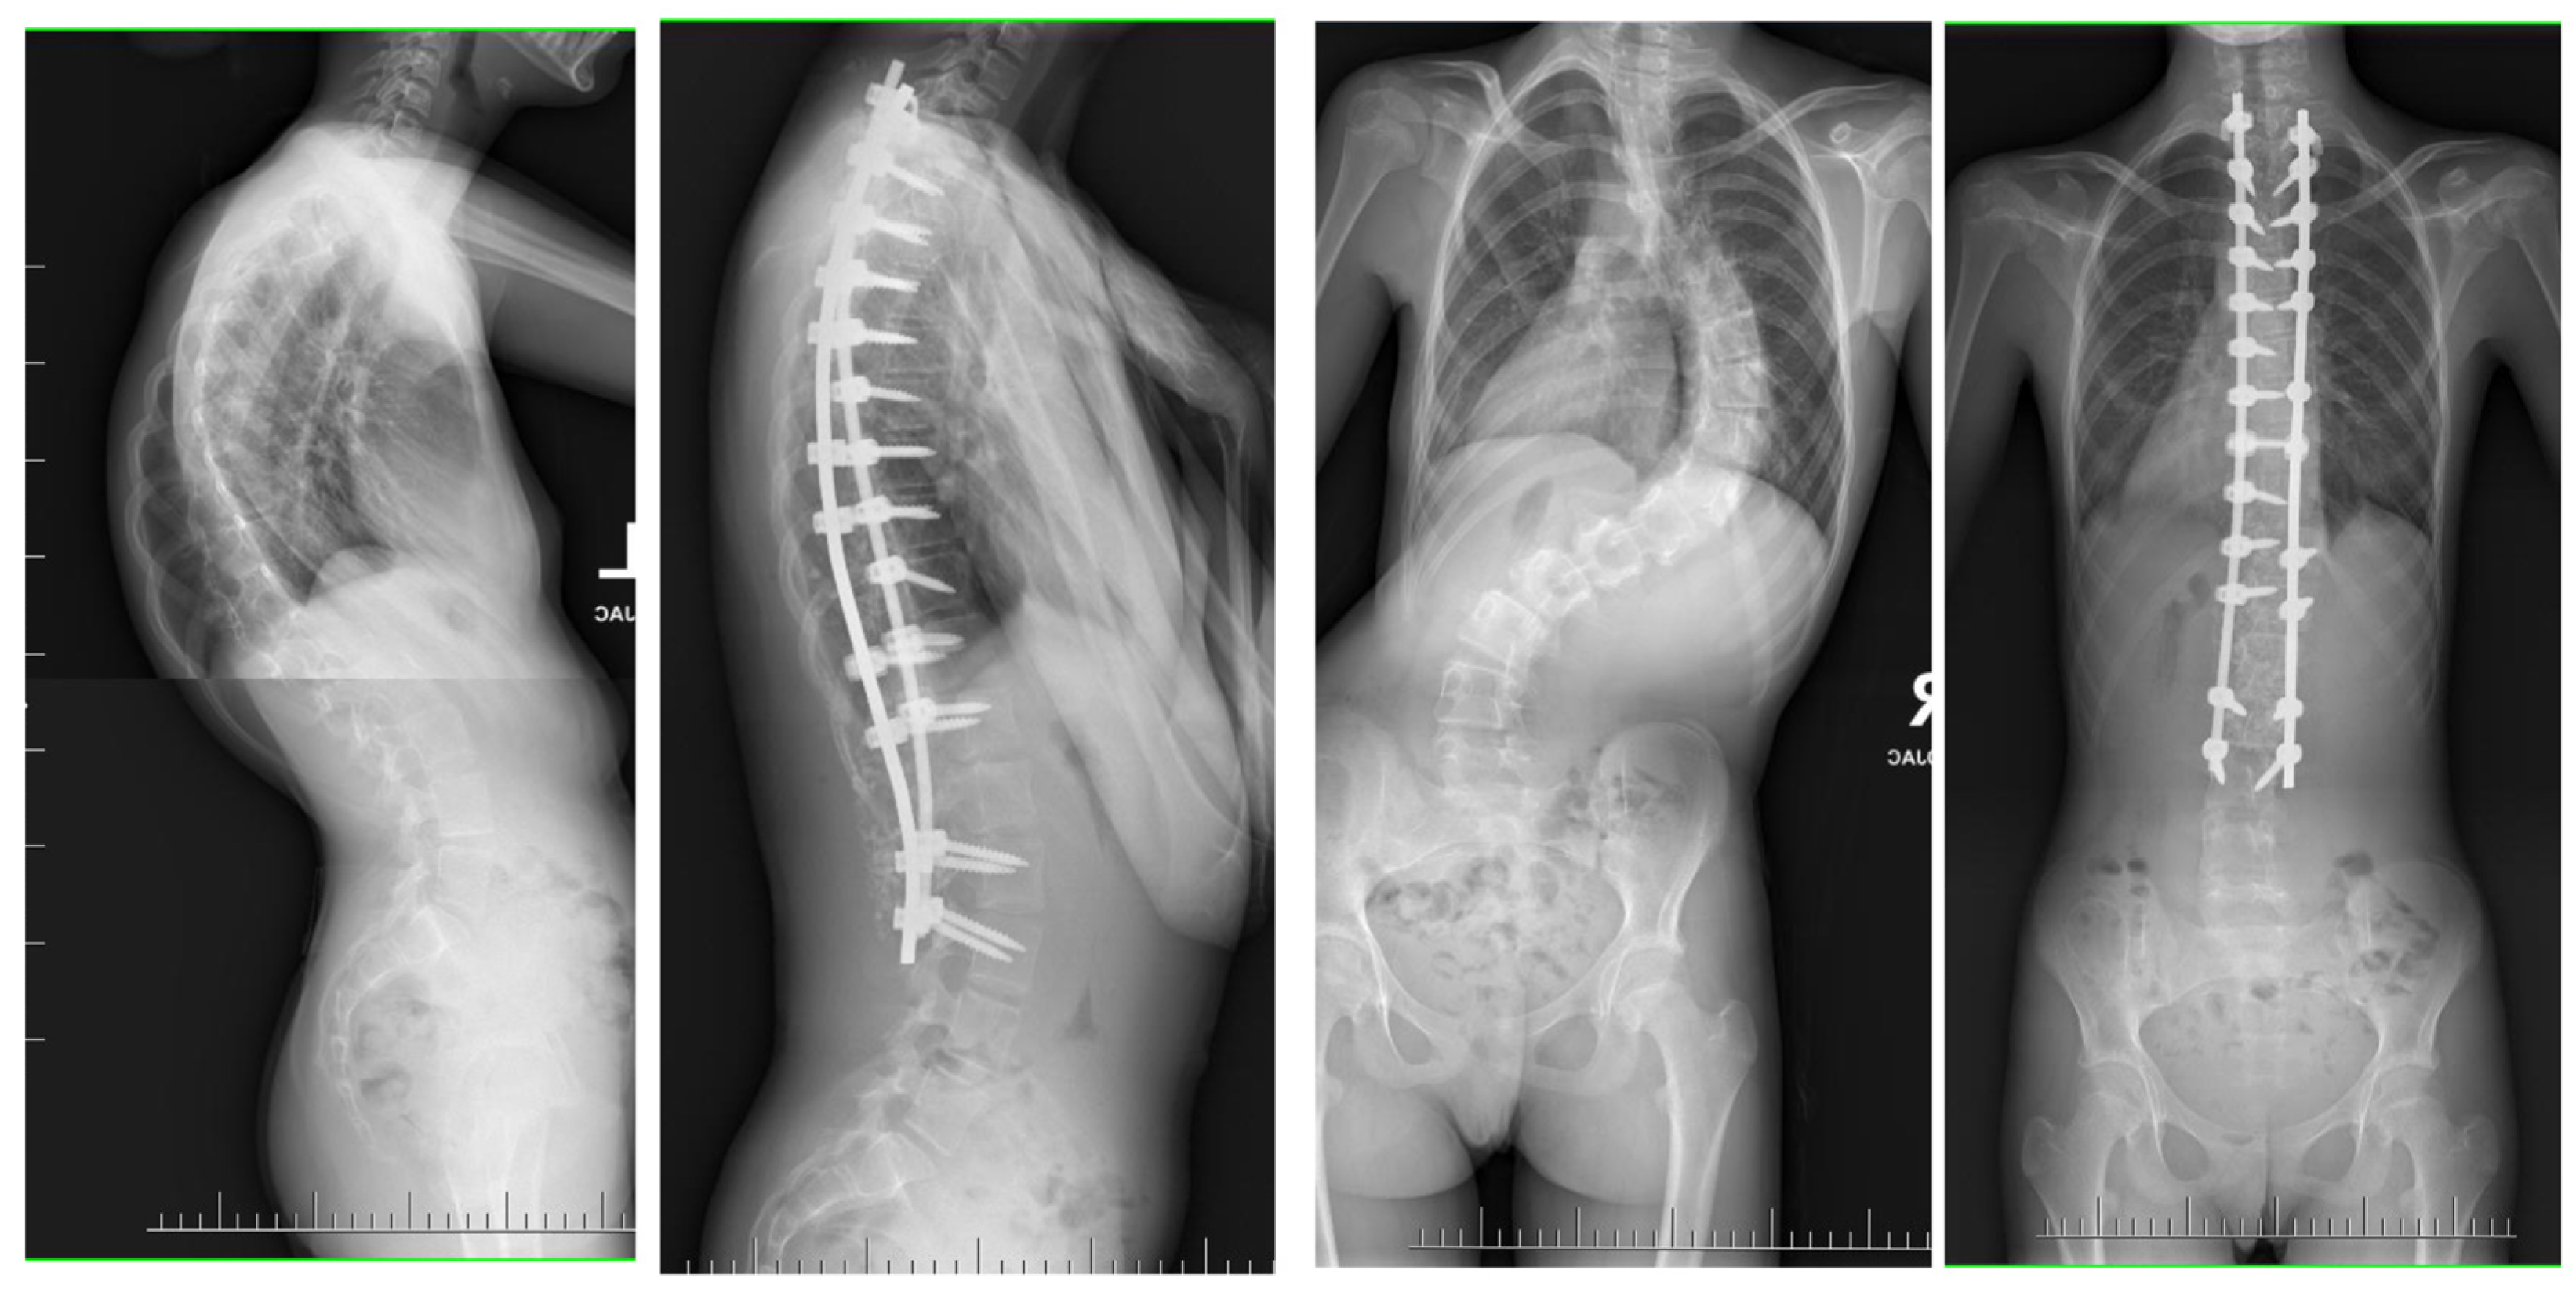

2. Material and Methods

11. Author’s Preferred Technique